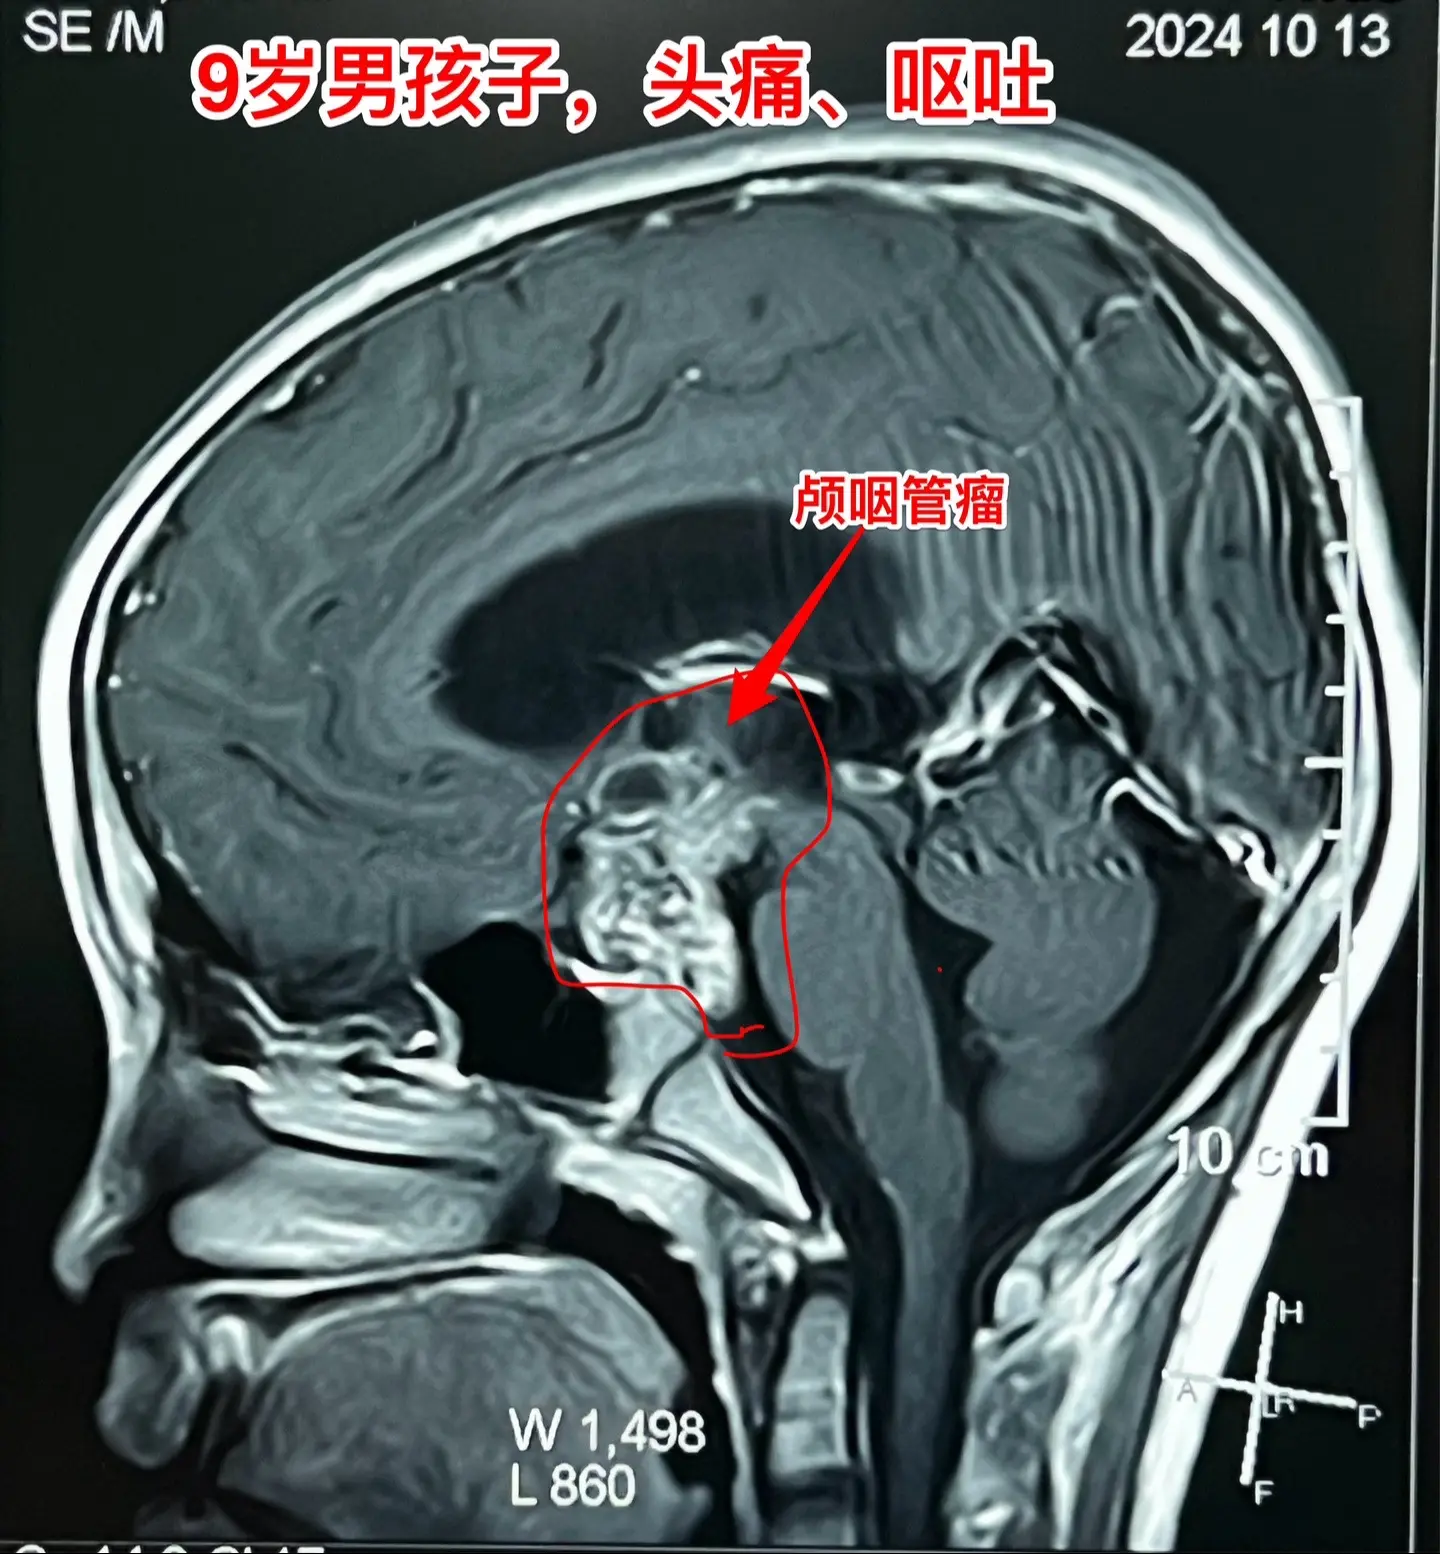

12岁南京男孩子头痛、呕吐。平时感觉身体很好,9月7日因头痛、呕吐到医...